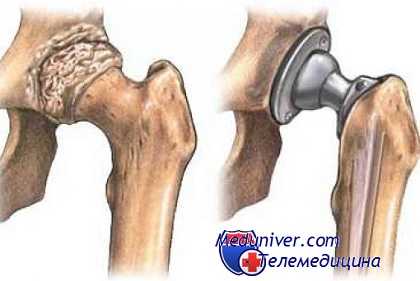

Хирургическое вмешательство

При неэффективности консервативного лечения, болях, не устраняемых медикаментозно, неуклонном прогрессировании коксартроза пациентам показано хирургическое вмешательство. Операция проводится сразу при патологии 3 степени тяжести, так как устранить возникшие деструктивные изменения хрящей и костей приемом препаратов или ЛФК невозможно.

Эндопротезирование

Замена тазобедренного сустава имплантатом производится под общим наркозом. Для профилактики развития инфекционного процесса назначается курсовой прием антибиотиков. Через 10 дней швы снимаются, а больной выписывается из медицинского учреждения. На этапе реабилитации пациентам показаны физиотерапевтические и массажные процедуры, ЛФК.